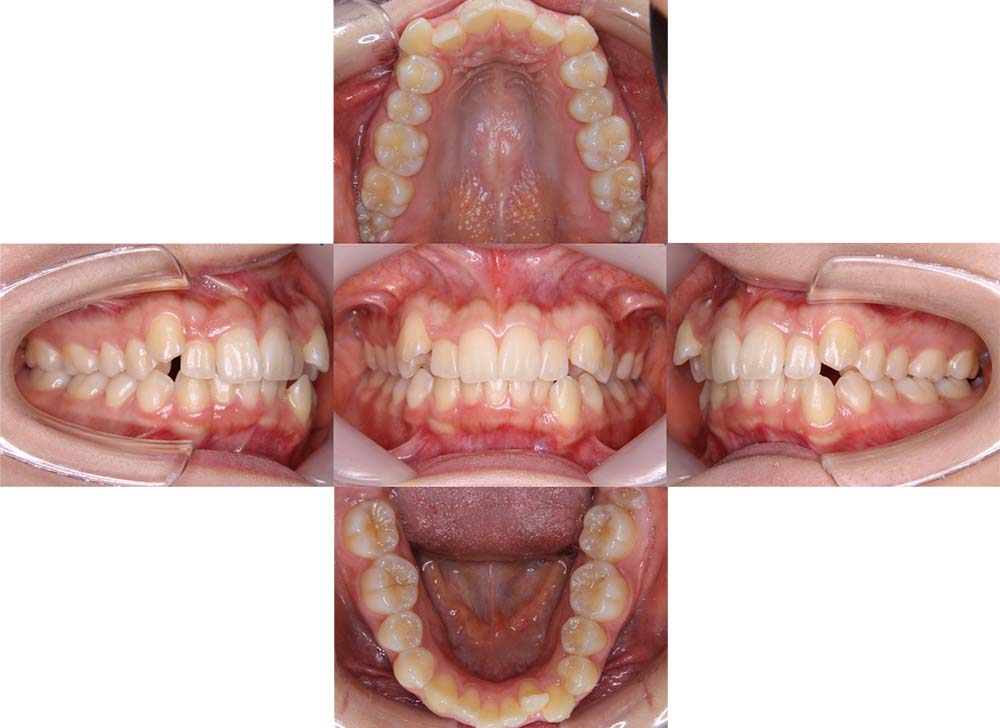

症例01

| 主訴 | 歯並びがガタガタしている。 |

| 診断名あるいは主な症状 | 叢生 |

| 年齢/性別 | 22歳・男性 |

| 矯正ステージ | 大人の矯正治療 |

| 治療方法 | ワイヤー矯正 |

| 抜歯部位/抜歯有無 | 非抜歯 |

| 治療内容 | 上顎大臼歯の遠心移動により前歯のガタガタを排列スペースを獲得し全顎的な排列を行った。 |

| 費用 | 85万円程度(2025.10時点の料金となります。) ※矯正基本料金、審美ブラケットを含む |

| 治療期間 | 2年4ヶ月 |

| 主なリスク・副作用 | 痛み、歯根吸収、歯肉退縮、虫歯、後戻り |